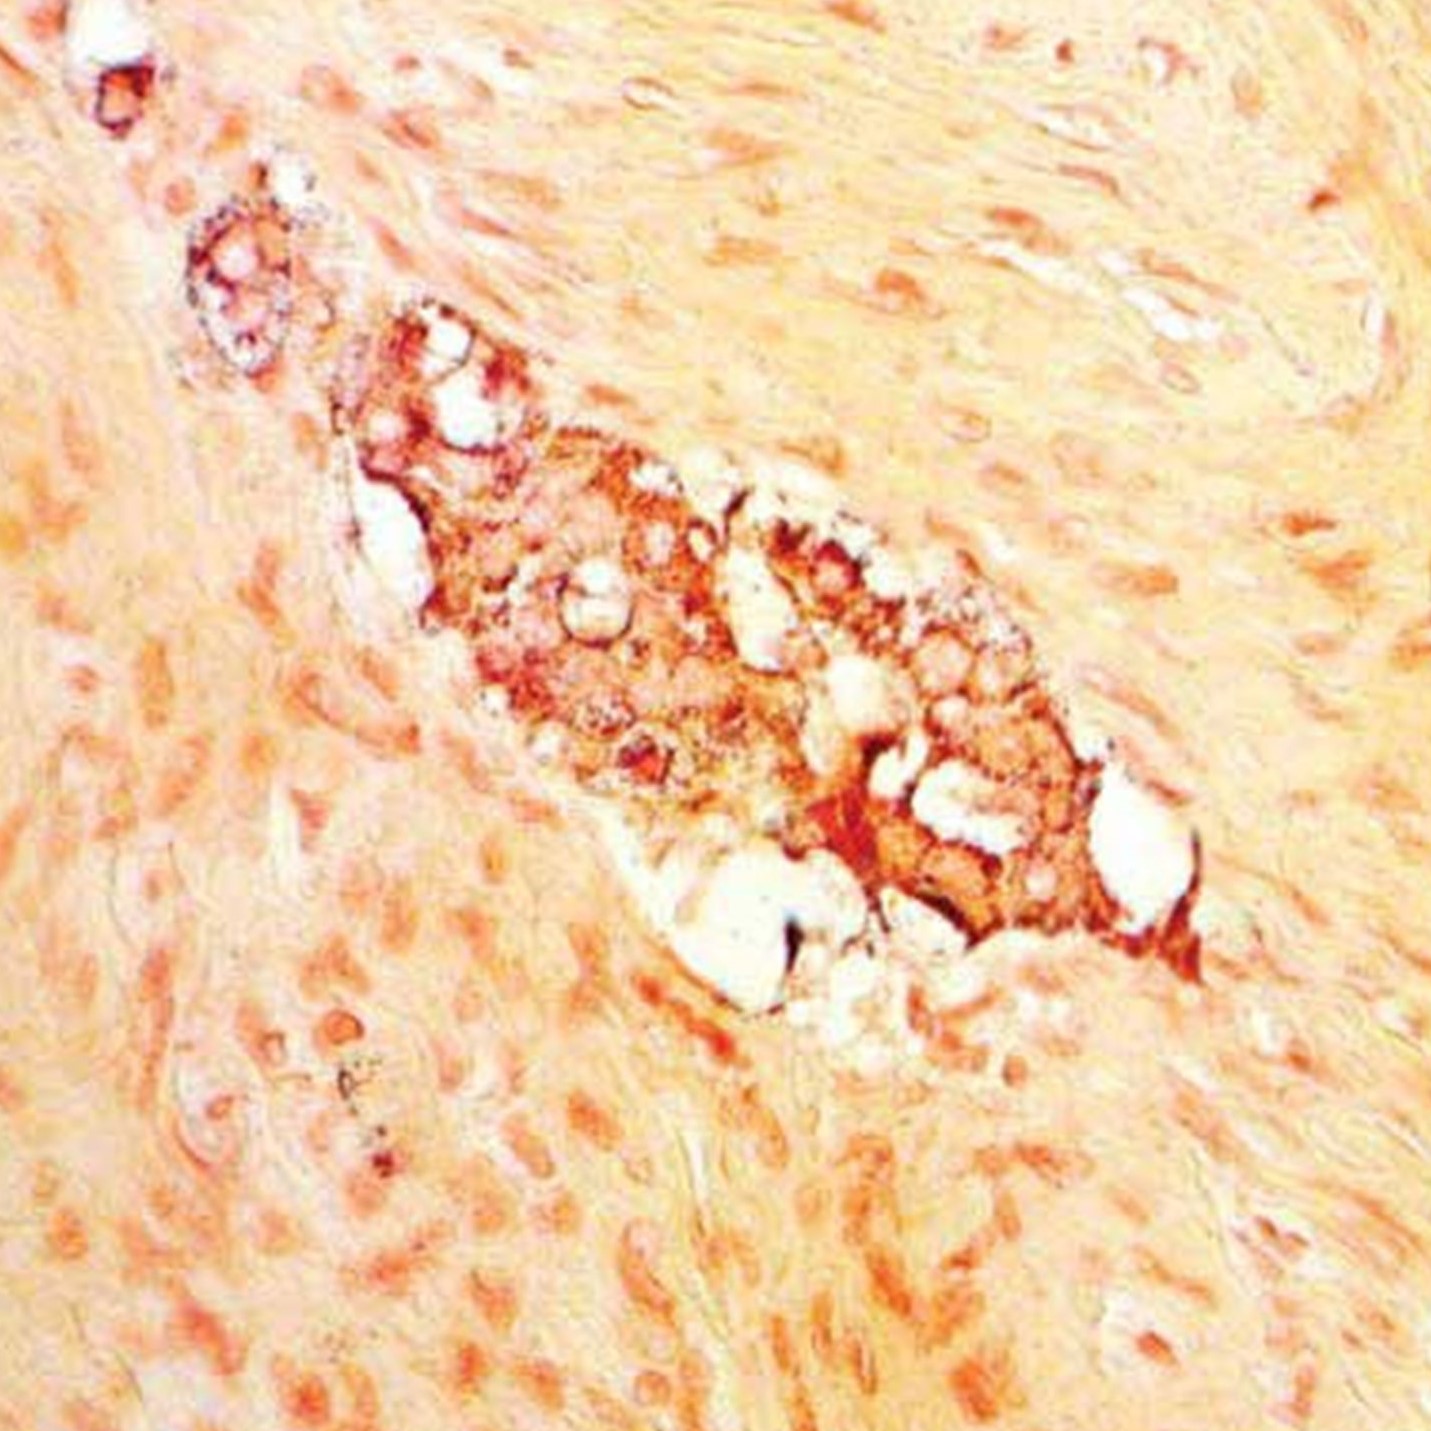

El kit de Grimelius se utiliza en histología para la visualización de estructuras argirofílicas en secciones de tejido histológico. Algunos tejidos, como los tumores neuroendocrinos, pueden unirse a los iones de plata de la solución de nitrato de plata, pero no reducirlos a la forma visible - plata elemental; por ello, la reducción de los iones de plata durante la tinción se consigue exponiendo la sección a la solución reductora de hidroquinona y sulfito de sodio. El exceso de iones de plata no unidos se elimina enjuagando la sección con una solución de tiosulfato de sodio.

Gránulos de argirófilo: marrón brillante a negro

Fondo: amarillo-marrón